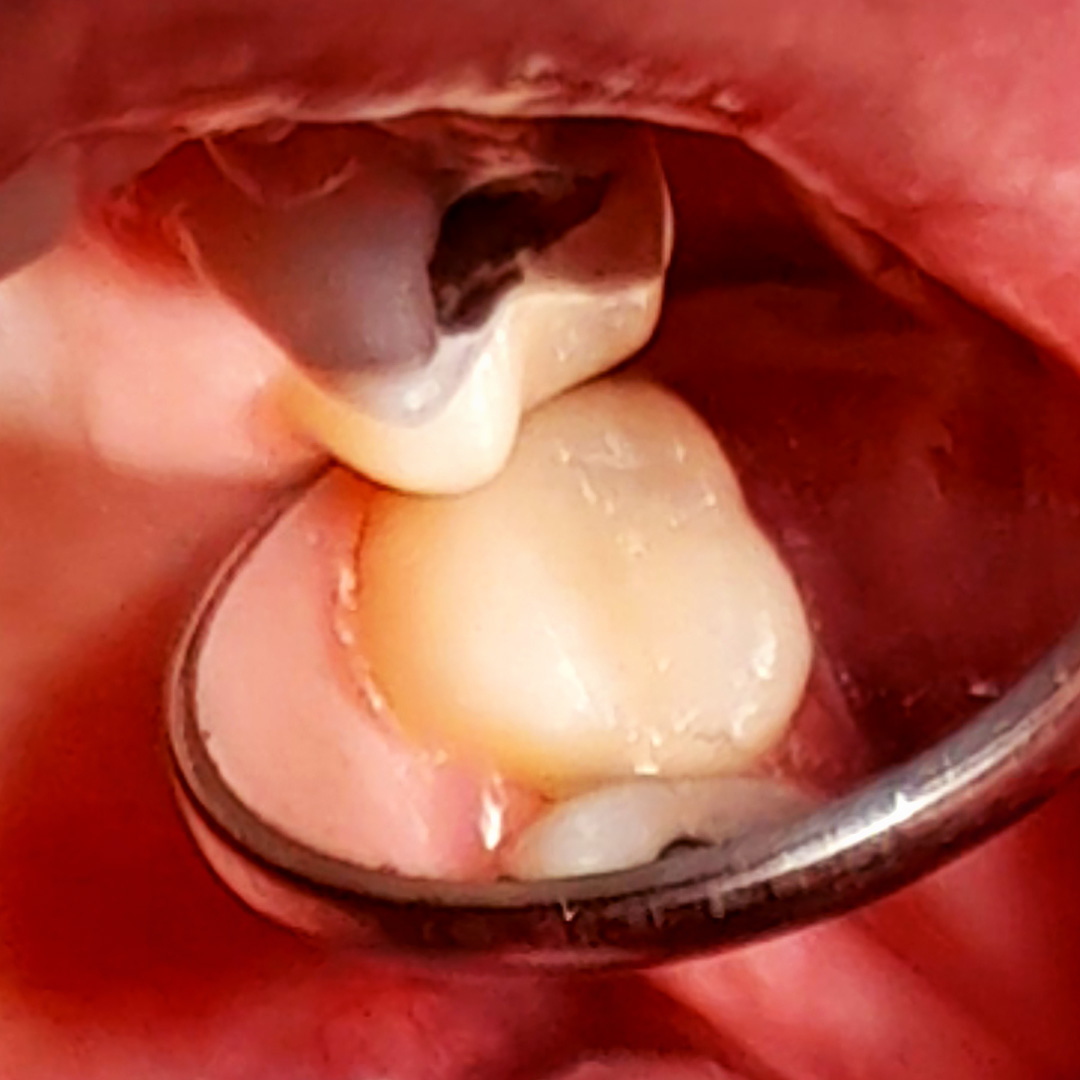

В «Стоматологию Комфорта» обратилась пациентка с жалобами на кратковременные боли от приёма холодных продуктов в области 27 зуба. В ходе осмотра врачом-стоматологом-терапевтом Похилько Н. Г. была обнаружена кариозная полость на жевательной поверхности 27 зуба. Зондирование было болезненно, перкуссия не вызвала реакции. Похилько Н. Г. провела ревизию и обработку полости под контролем кариес-маркера. Был поставлен диагноз: хронический глубокий кариес 27 зуба окклюзионно. Врач принял решение о лечении кариеса с установкой пломбы из материала Estelite.

- постановка пломбы из композита Estelite;

- шлифовка и полировка пломбы;